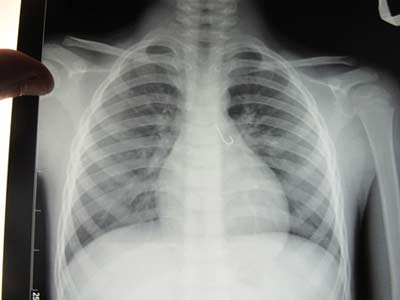

Bản chụp X-Quang thấy rõ lưỡi câu mắc trong phổi bệnh nhi

Bệnh nhi N.X.T 7 tuổi, là người dân tộc Cơ tu thường trú tại huyện Nam Trà My, tỉnh Quảng Nam. Trước đó, ngày 10/9, bệnh nhi nhập viện trong tình trạng ngột thở, ho sặc sụa. Qua nội soi cấp cứu, phát hiện 1 lưỡi câu còn nguyên móc, dài 1,5cm mắc ở phổi. Lưỡi câu cắm vào niêm mạc của phế quản. Các bác sĩ đã tiến hành phẫu thuật cấp cứu lấy lưỡi câu ra khỏi phổi bệnh nhi an toàn. Qua theo dõi điều trị, hiện sức khỏe bệnh nhi đã bình phục hoàn toàn.